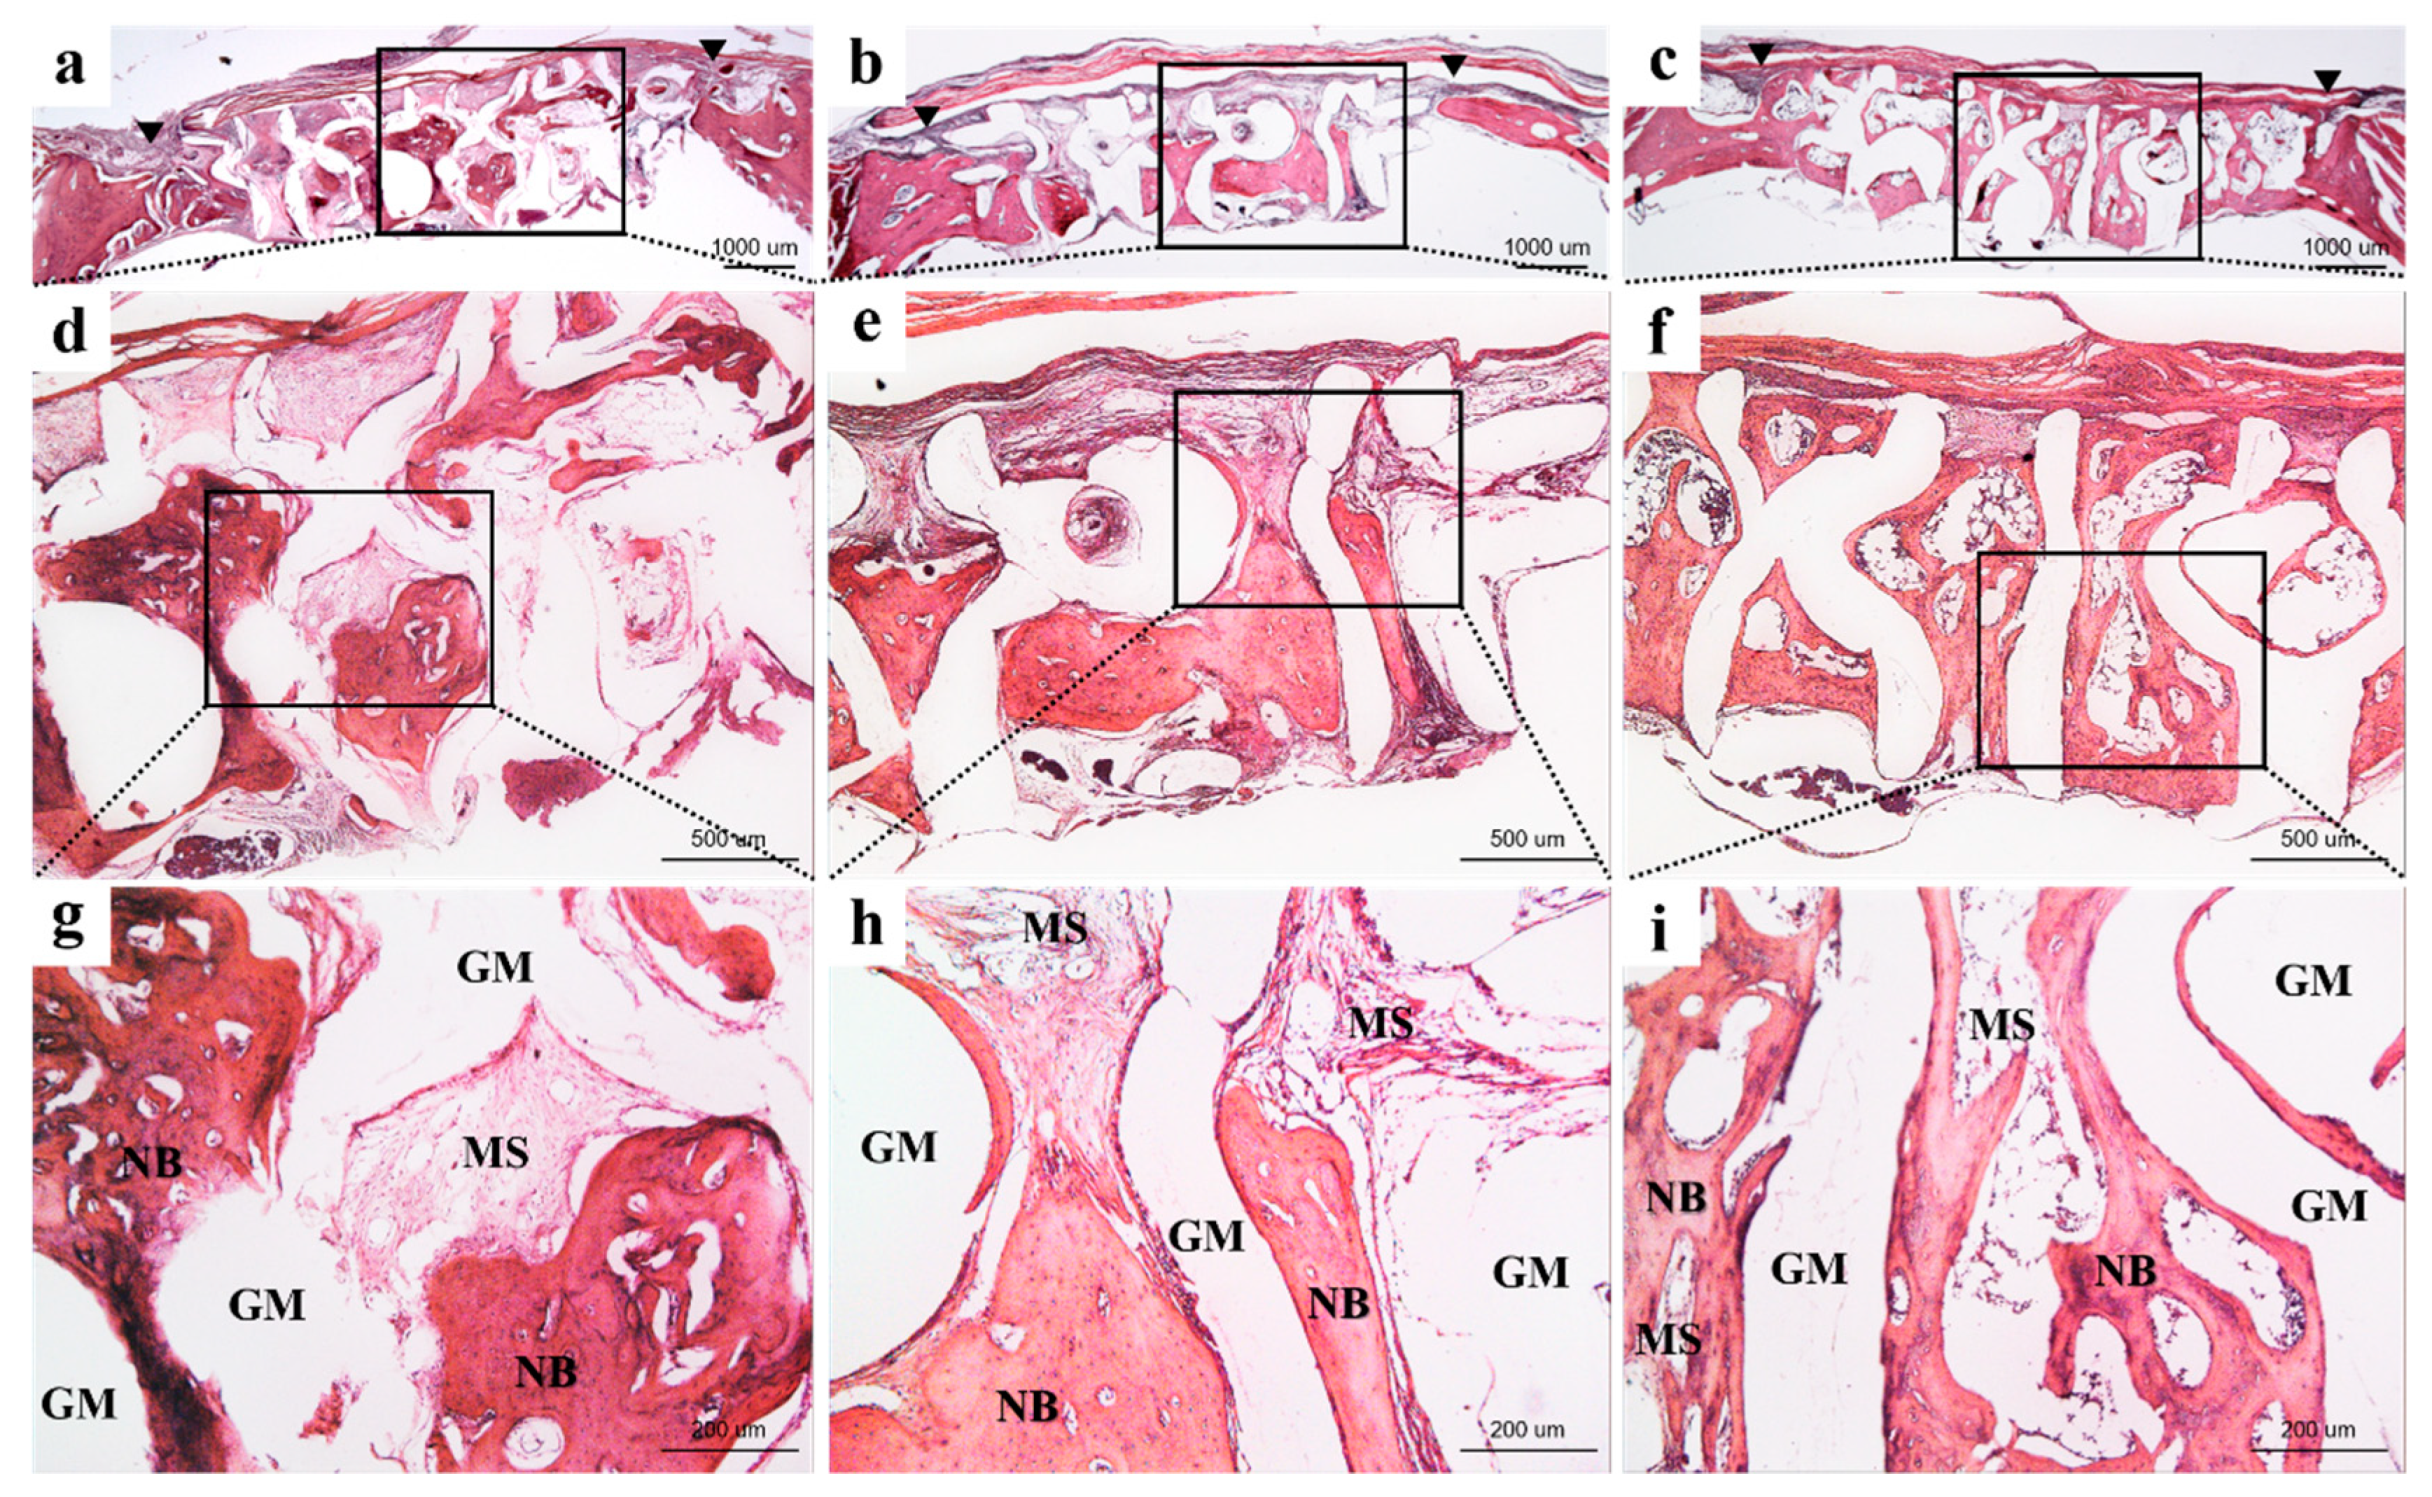

3.2.3. Histological Findings

3.2.4. Histometric Findings